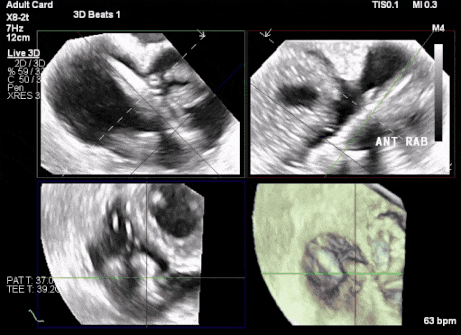

術中TEE觀察夾持件的位置